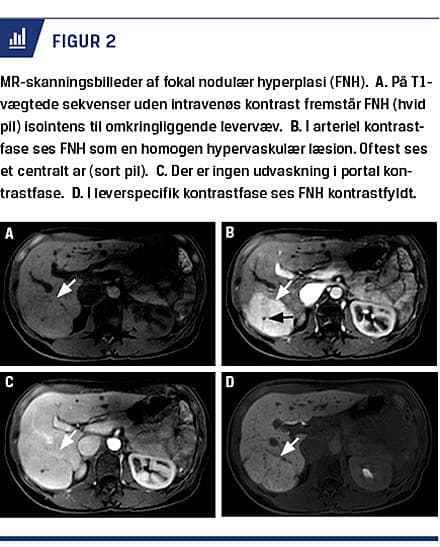

FNH fremstår billeddiagnostisk som en solid tumor: på UL-skanning homogen isoekkoisk, på CT velafgrænset isodens og på MR-skanning henholdsvis T1- og T2-vægtede sekvenser isointens og svagt hyperintens. Et centralt ar ses i 60% af læsionerne. Med i.v.-kontrast fremstår FNH ved UL-skanning, CT og MR-skanning som en homogen opladende hypervaskulær tumor uden udvaskning. Ved kontrast-UL-skanning ses centrifugal spoke-wheel-kontrastfyldning i arteriel fase hos en tredjedel pga. initial fyldning af centralt fødekar og dernæst af multiple små kar radiært-perifert [16].

På MR-skanning med leverspecifik kontrast (Figur 2), som optages og omsættes i fungerende hepatocytter, fremstår FNH i leverspecifik fase kontrastfyldt [17]. Denne billedmodalitet er den bedste til skelnen mellem FNH og HCA, der ligeledes er hypervaskulær, men uden normalt fungerende galdeveje og således med kontrastdefekt i leverspecifik fase [18].